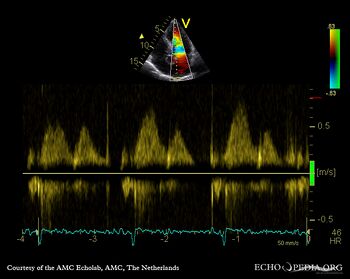

| Pulsed-wave Doppler signal of mitral inflow: impaired relaxation | Pulsed-wave Doppler signal of pulmonary venous flow |